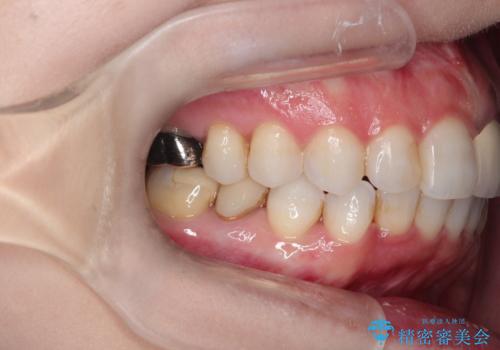

インビザラインによる非抜歯矯正 ガタガタな歯並びを整った歯並びへ

- 上下の全体的ながたつきが気になるとのことで来院されました。

マウスピースでの目立たない矯正を希望されたので、インビザラインでの治療となりました。

全体的に歯と歯の間にわずかに隙間を作り、歯を並べました。